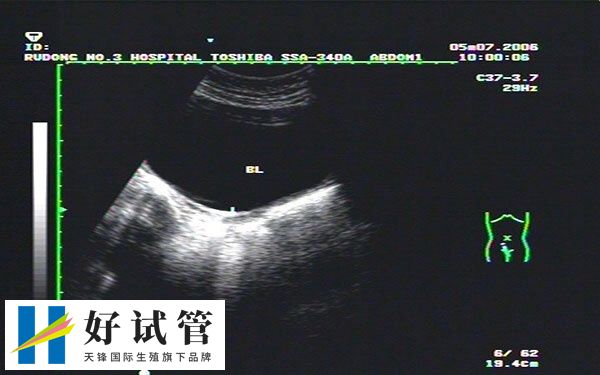

2、根据超声检查结果

超声检查可以确定受精卵的发育情况和大小,从而确定怀孕周数和预产期。通常在孕早期进行第一次超声检查,这时候可以看到胎儿的心跳。根据胎儿大小和发育情况来确定怀孕周数和预产期。